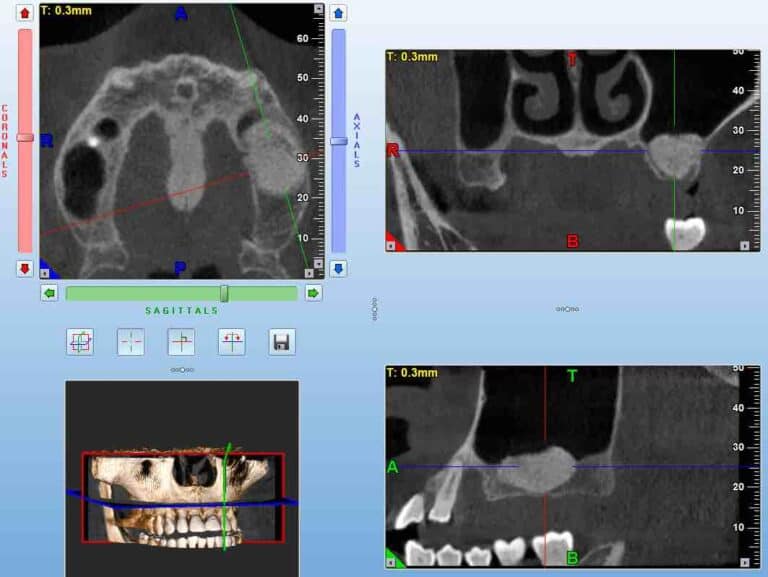

A Cone Beam CT is compiling 3D data, but it still allows us to access it only through 2d representations (slices) in a flat 2D screen. The surgeon has to read these combined 2D images and reconstruct a mental 3D structure of the surgical anatomy, certainly not an easy task to do with precision.

Note here that although the data we aquire from a CBCT are 3-dimensional, in reality the representation is still 2D: we only see it in a flat screen. To recreate a truly 3D representation you will need to 3D print the data from the CBCT. This is actually a very powerfull teaching medium, which we have often utilised in complex surgeries. 3D printing the anatomy prior to surgery allows you to test different techniques and access points with safety, before you choose the best way to go in (or sometimes to not go in at all).

A Challenging surgical case with a complex of vertical and horizontal septa in the posterior sinus. Segmentation of the 3D radiographical and optical data and 3D printing in multiple layers from AMMA Ltd Hong Kong, has allowed for an accurate representation of the anatomy where multiple surgical access approaches were tested.

An important question for everyone. Do not mix SRA with other surgical skills such as cutting and suturing, SRA is an underlying skill. It will “naturally” grow with every surgery, but if you want to excel it you have to target it with specific training, just like anything else. And if you want to test your level, you also need some specific test. Many tests are available to test SRA, most of them are very generic though. Some time ago with Dr. James Chow and Dr. Coral Yao we developed a test specific to understanding surgical anatomy with the use of CBCT. The challenge here is to reconstruct a 3Dimensional anatomic space from 3 2D representations, as we routinely have to do while “reading” a CBCT. The test was called DASRA and was scientifically validated. It will give you an idea of the level of an important skill for implant surgery and it’s available online for free. Take the DASRA challenge and remember to leave us your thoughts and comments.